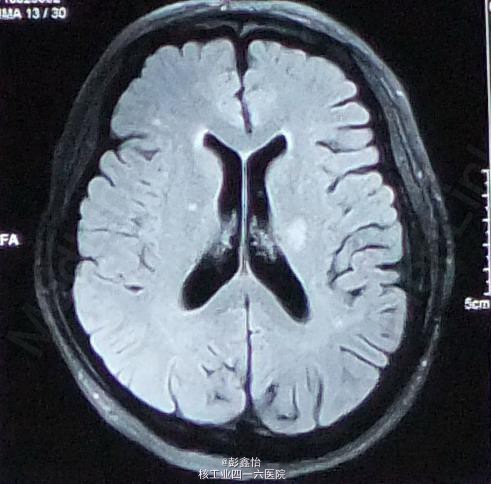

PE: NE:神经专科查体均正常; ABCD2评分为3分 NIHSS评分为0分; 入院后辅助检查均正常,CT、MRI+MRA、脑电图、视频脑电监测均未见异常。

因患者无明显肢体抽搐及局部泛化过程,脑电监测正常,基本可除外癫痫发作。诊断TIA,予以阿司匹林、他汀降脂等治疗,但TIA继续发作。 追加血管评估,但TCD、DSA、颈部血管超声均未发现异常,在原有治疗基础上,予以双抗、改善循环、营养神经加强治疗 但患者仍频繁发作TIA,3天内共发作20余次。判断为治疗抵抗,继续加用抗凝、脑保护,最后加用羟乙基淀粉扩容治疗后发作终止,但患者出现右侧肢体轻偏瘫。 复查DWI:左侧基底节区出现急性梗死灶; 复查MRA、DSA均未见异常。